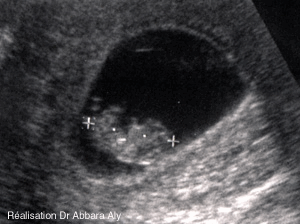

AActivité cardique à 10 SA